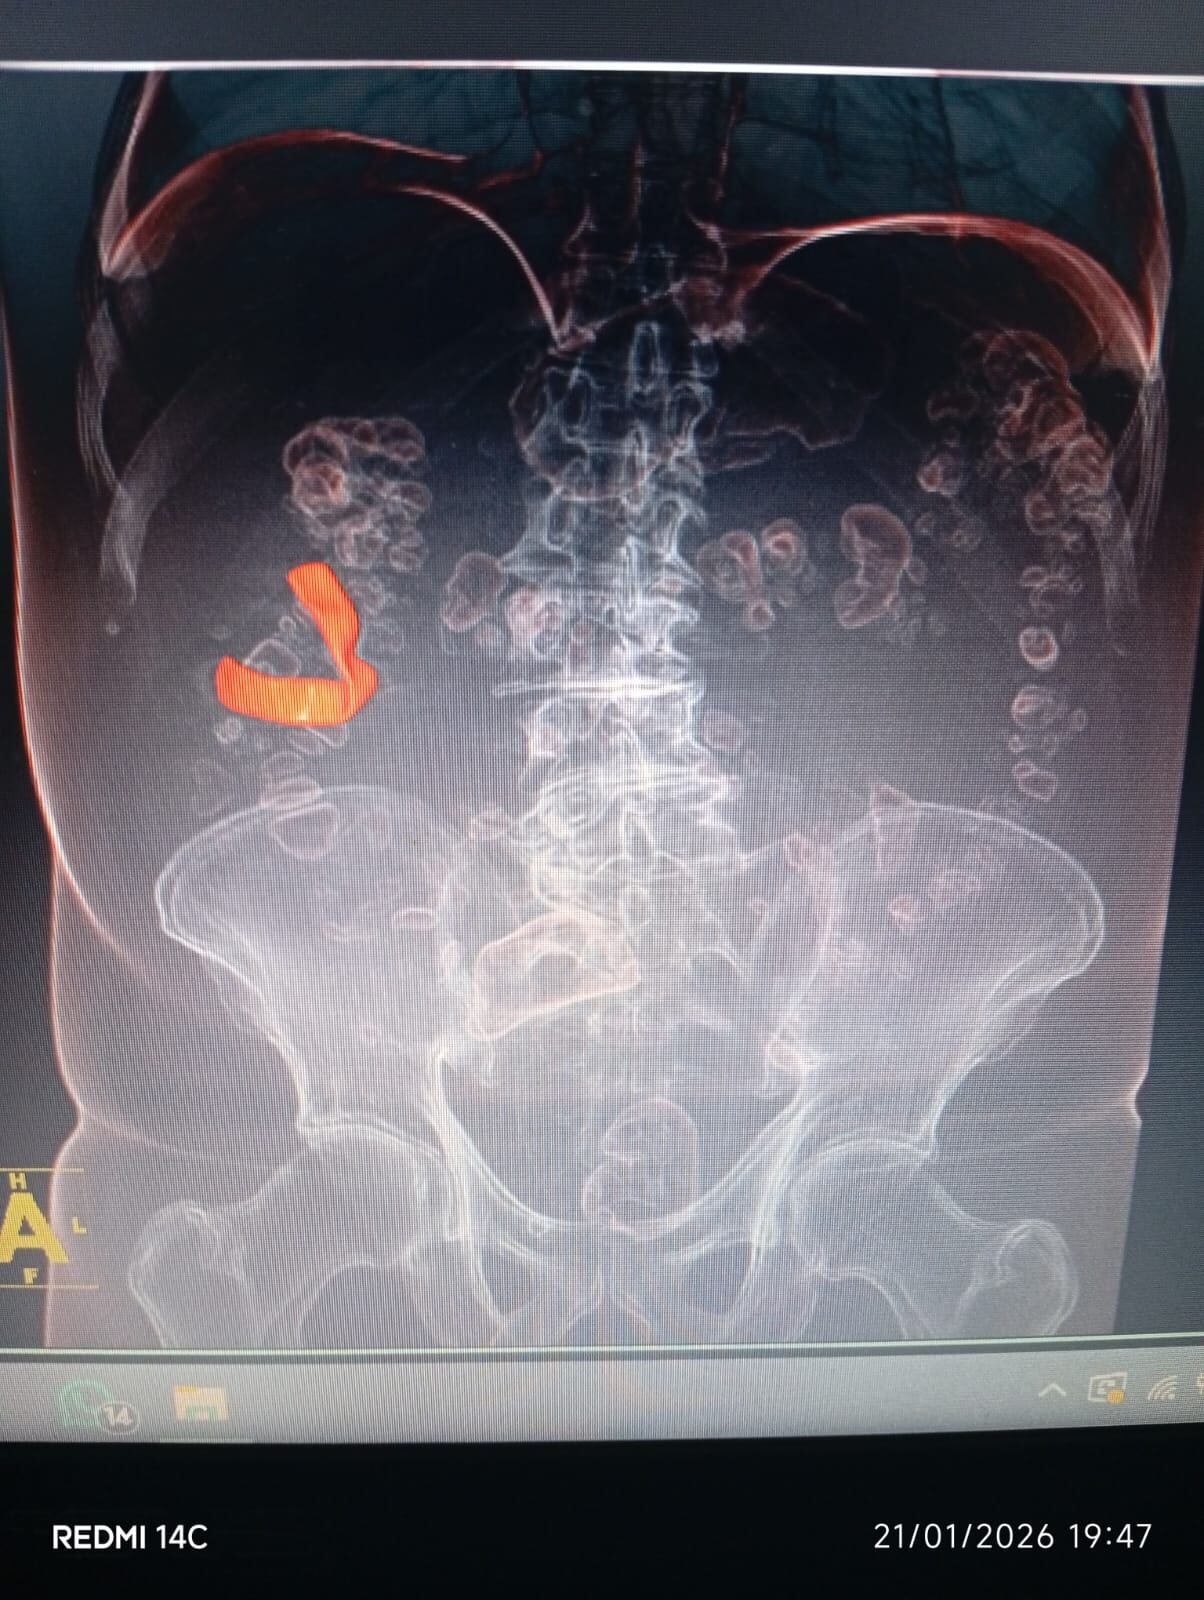

“Durante años acudió a consultas médicas por estos síntomas, pero al ser considerados leves, únicamente se le formulaban medicamentos y reposo”, explicó. Sin embargo, la situación cambió en diciembre de 2025, cuando, tras la realización de exámenes de rutina, una radiografía evidenció la presencia de un cuerpo extraño en su organismo.

Posteriormente, mediante estudios imagenológicos adicionales como ecografías, se logró confirmar la existencia del elemento, el cual, según indicó la defensa, se presume sería una gasa quirúrgica o compresas que habría quedado en el cuerpo durante la intervención realizada en 2018.